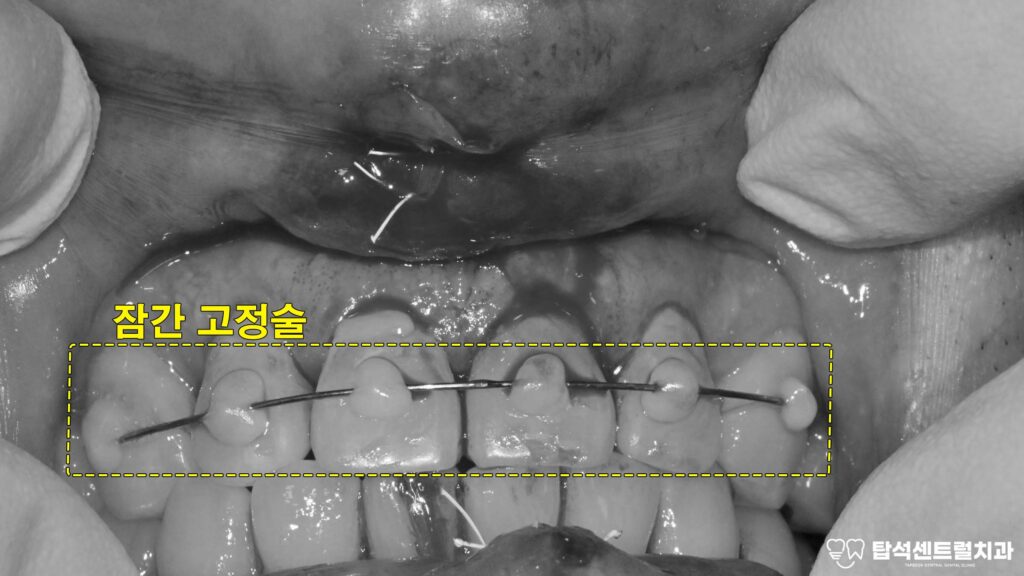

잠간고정술이란 무엇인가요?

잠간고정술은 동요도가 있는 부위를

일정 기간 묶어서 안정시키는

방법입니다.

충격을 받아 빠질 뻔한 상황이거나

잇몸 질환으로 인해 동요도가

심해졌을 때 시행하게 됩니다.

문제가 있는 부위뿐 아니라

양옆의 건강한 곳까지 함께

와이어로 연결하여 묶어줍니다.

용현동 치과 에서 보여드리는

케이스의 경우에는 앞니부터 송곳니까지

이어지는 치아 (#13=12=11=21=22=23) 6개에

와이어를 부착하였습니다.

잠간고정술 시행 과정

이 시술을 시행할 때는 전치부와

주변 부위를 와이어로 연결합니다.

예를 들어 윗쪽 송곳니부터

반대편 송곳니까지 총 6개를

함께 묶을 수 있습니다.